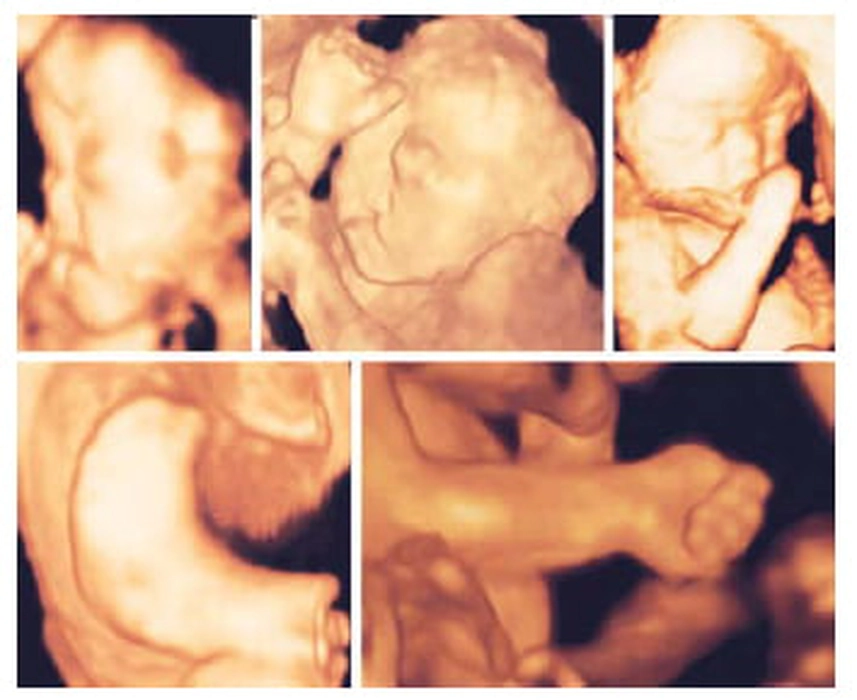

Ce presupune o morfologie fetală în trimestrul 1? Iată de ce este atât de importantă evaluarea în această perioadă!